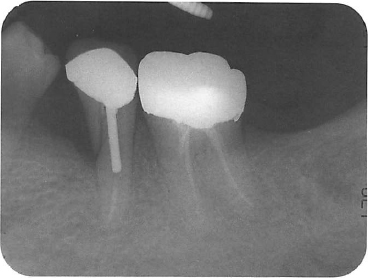

Fig. 1.–Example of an upper right premolar in an apparently precarious situation. a. No root filling is evident, the canals are calcified, there is a large bulky post with a near perforation and a periapical area. b, Nevertheless, this case could be salvaged by removal of the post and crown, finding and cleaning two canals and root filling. c. Healing is evident six months later, following which the tooth could be restored.